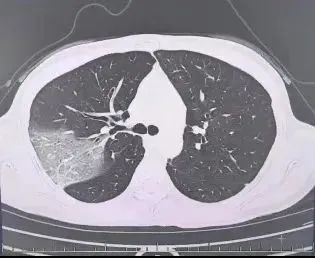

结果情况反而进一步加重:好几叶肺都出现了“白肺”现象,指间血氧饱和度只有88%,血心肌酶谱、肌钙蛋白的指标、肝功能的指标也出现了明显的异常。

流感(重型)!程女士立即被安排住院治疗。医院呼吸科团队迅速制定了一套个性化的诊疗方案,在悉心救治下,7天后,程女士顺利康复出院。